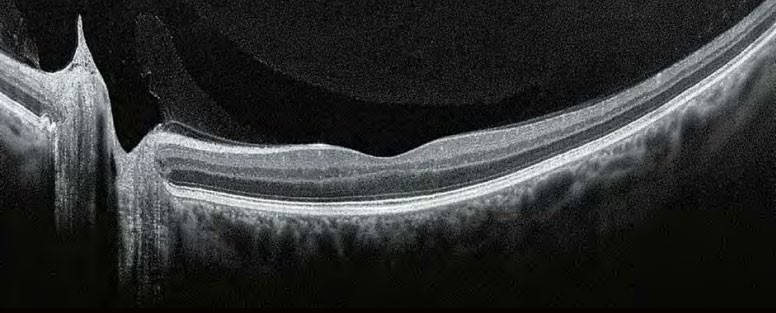

Завдяки визнаній оптиці Canon, Xephilio OCT-A1 пропонує чудову якість зображення. З цифровою розподільчою здатністю до 1.6 мкм система дозволяє чудово диференціювати структури та окремі шари сітківки.

Xephilio OCT-A пропонує відмінну оптичну розподільну здатність. Усередненням безлічі сканів (до 200)досягається прекрасна якість зображення з дивовижною деталізацією.

За допомогою Xephilio OCT-A1 ви можете усереднити до 200 сканувань, щоб досягти розподільчої здатності зображення, що дозволяє детально бачити як структуру шарів сітківки, так і пошарову структуру скловидного тіла. Для оптимальної візуалізації система пропонує спеціальні режими сканування для скловидного та судинного зображення, а також особливо широку ширину сканування до 13 мм

Надійне розпізнавання 10 шарів

Xephilio OCT-A1 компанії Canon може автоматично виявити та розрізнити 10 шарів сітківки, включаючи мембрану Бруха (BM) - завдяки чудовій якості зображення та розподільчій здатності.

НЕЙМОВІРНА ДЕТАЛІЗАЦІЯ